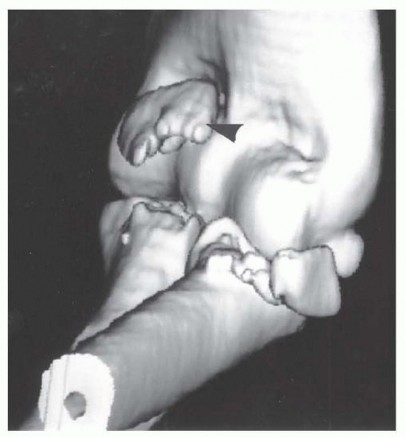

Meticulous preoperative planning is the cornerstone of a successful surgical outcome in elbow fracture-dislocations. High-quality plain radiographs in the anteroposterior (AP) and lateral planes must be obtained before and after any closed reduction attempts. However, cast material and overlapping osseous structures often obscure critical bony detail. Therefore, computed tomography (CT) scanning with thin cuts, multiplanar reformatted images, and three-dimensional (3-D) reconstructions is considered the gold standard and is mandatory for surgical planning. 3-D CT allows the surgeon to precisely understand the size, comminution, and spatial orientation of the coronoid and radial head fragments, dictating whether primary osteosynthesis is feasible or if arthroplasty will be required.

Coronoid fractures are equally critical to evaluate, as the coronoid provides the anterior buttress preventing posterior subluxation of the ulna. These have been traditionally classified by Regan and Morrey: Type I (tip avulsions, often representing capsular avulsions rather than true osseous stabilizers), Type II (less than 50% of the coronoid height), and Type III (more than 50% of the coronoid, often involving the sublime tubercle and MCL insertion). However, modern biomechanical understanding emphasizes the anteromedial facet fracture, a distinct entity caused by a primary varus force. The medial facet is paramount for varus stability of the elbow. These fractures are inherently unstable and are best treated with open reduction and internal fixation utilizing a medial buttress plate, as failure to recognize and stabilize the anteromedial facet will lead to rapid articular wear and chronic varus instability.